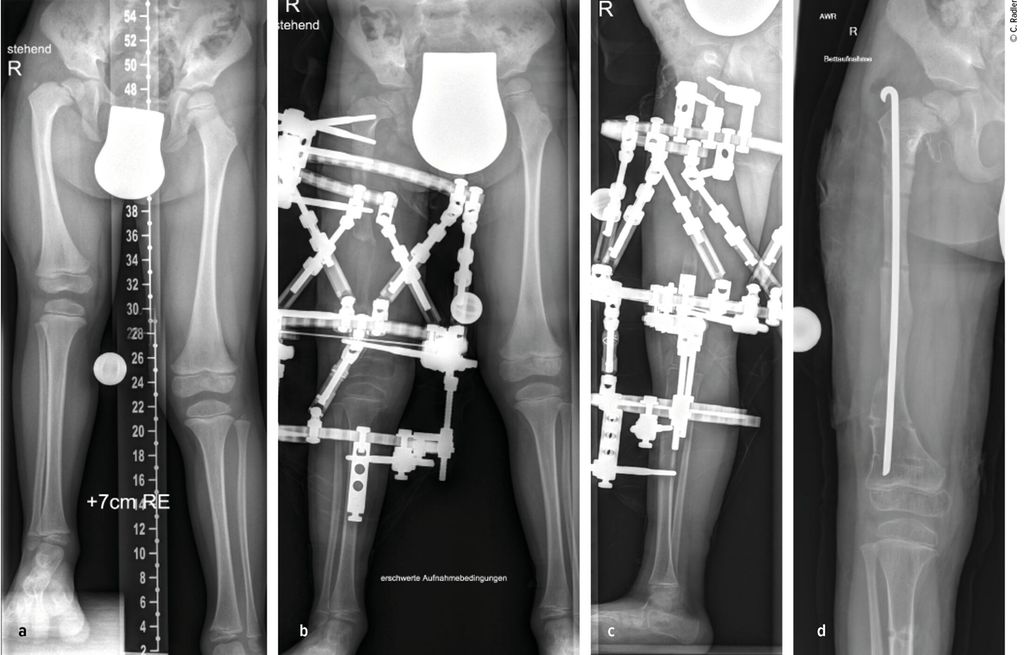

Sowohl beim CFD wie auch bei der FH zeigen sich deutliche Pathologien am Kniegelenk. Es besteht eine Hypoplasie der lateralen Epiphyse mit entsprechenden Wachstumsstörungen, was zu einem rezidivierenden Valgus am Kniegelenk führt.3,4 Zusätzlich besteht in vielen Fällen eine deutliche Instabilität des Kniegelenkes. Es findet sich eine Hypoplasie des ACL in etwa 15% und ein vollständiges Fehlen des ACL in etwa 85% der Fälle.5 Das PCL ist in etwa 21% hypoplastisch und in etwa 24% ebenso fehlend. Diese Instabilität des Kniegelenkes ist bei milden Formen oft klinisch im Alltag nicht relevant, kann jedoch während einer Verlängerung zu massiven Problemen im Sinne von Luxation und Subluxation führen. Zusätzlich zeigt sich oft eine Lateralisation der Patella, wobei diese auch permanent luxiert lateral am Femurkondyl liegen kann.

Die Valgusstellung kann sehr einfach über eine Wachstumslenkung (Hemiepiphysiodese mit 2-Loch-Platte) korrigiert werden. Um eine Subluxation am Kniegelenk zu verhindern, muss bei allen diesen Fällen bei Verlängerung mit Fixateur dieser knieüberbrückend montiert werden (Abb.4). Bei Verlängerung über einen Verlängerungsmarknagel wird in diesen Fällen eine Oberunterschenkelschiene (KAFO) verwendet und prophylaktisch, soweit noch vorhanden, die Fascia lata auf Höhe des oberen Patellapols durchtrennt. Bei deutlicher Instabilität oder auch Subluxation ist eine Stabilisierung über eine komplexe Operation, die als Super-Knee-Operation subsumiert wird, erforderlich.2 Diese Operation kann auch an die Hüftrekonstruktion/Super-Hip-Operation angeschlossen werden, da hier die Faszie ohnehin präpariert wird. Je nach Alter des Patienten und dem Ausmaß der Instabilität wird hierbei die Fascia lata nach Präparation bis an das Tuberculum Gerdyi und Halbieren der Länge nach entweder extraartikulär oder intraartikulär geführt. Auch die Fixation wird abhängig vom Alter mit Biotenodeseschrauben oder Weichteilzügelung durchgeführt.

Abb. 4: Platzierung (a–d) eines Fixateur externe mit Knie-Überbau (e–g) zum Schutz vor (Sub-)Luxation